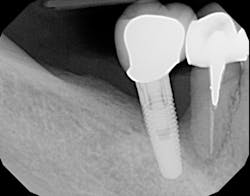

The most critical aspect of any implant system is the interface between the implant fixture and its surrounding bone (figures 1-5). Integration between the fixture and its surrounding bone is the foundation of modern implant dentistry. There is little we can do to modulate bone healing, but we can modify the implant fixture itself.

Figures 1-5: Figures 1 through 4 illustrate, respectively, a seven-year follow-up visit and a three-year follow-up visit of two different implant systems. Implant No. 22 (figure 5) shows peri-implant radiolucency following functional loading, indicating fibroencapsulation and loss of integration into bone, necessitating removal.